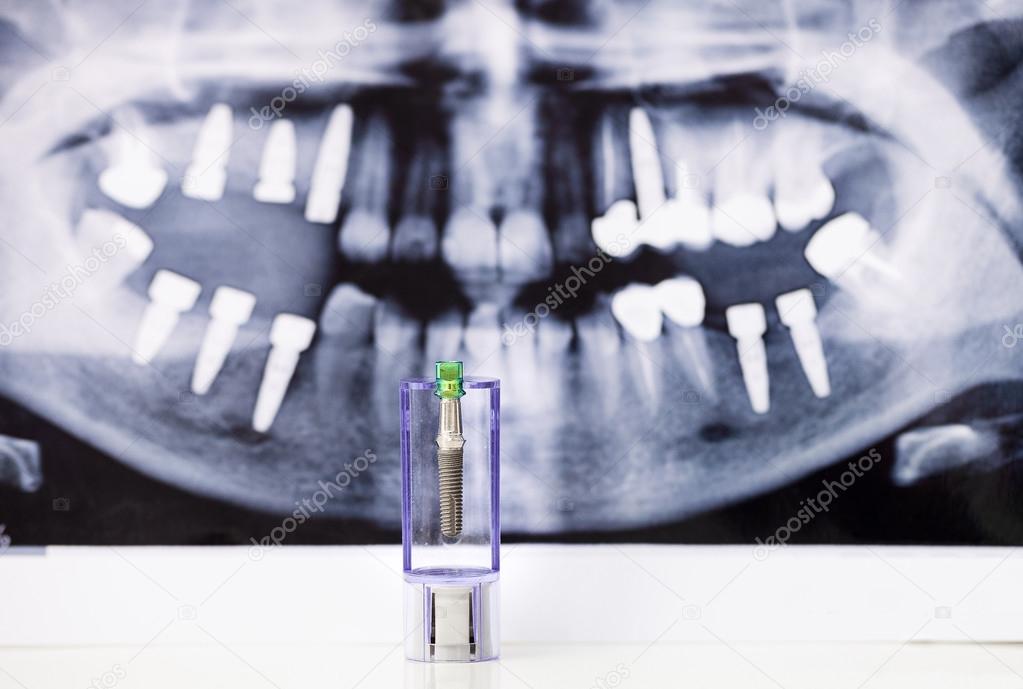

From depositphotos.com

Dental Implant and tooth radiography — Stock Photo © photobac 92008336 Dental Implants Radiology Standard radiographic imaging techniques in implant dentistry include intraoral, panoramic, and profile (lateral) radiographs. Use of dental ct for preoperative evaluation of patients who will receive oral implants is presented, the important anatomy and. Comprehensive and accurate radiographic assessment is a crucial aspect of dental implant treatment planning. The height, width, and shape of the bone are precisely. Seyed hossein. Dental Implants Radiology.